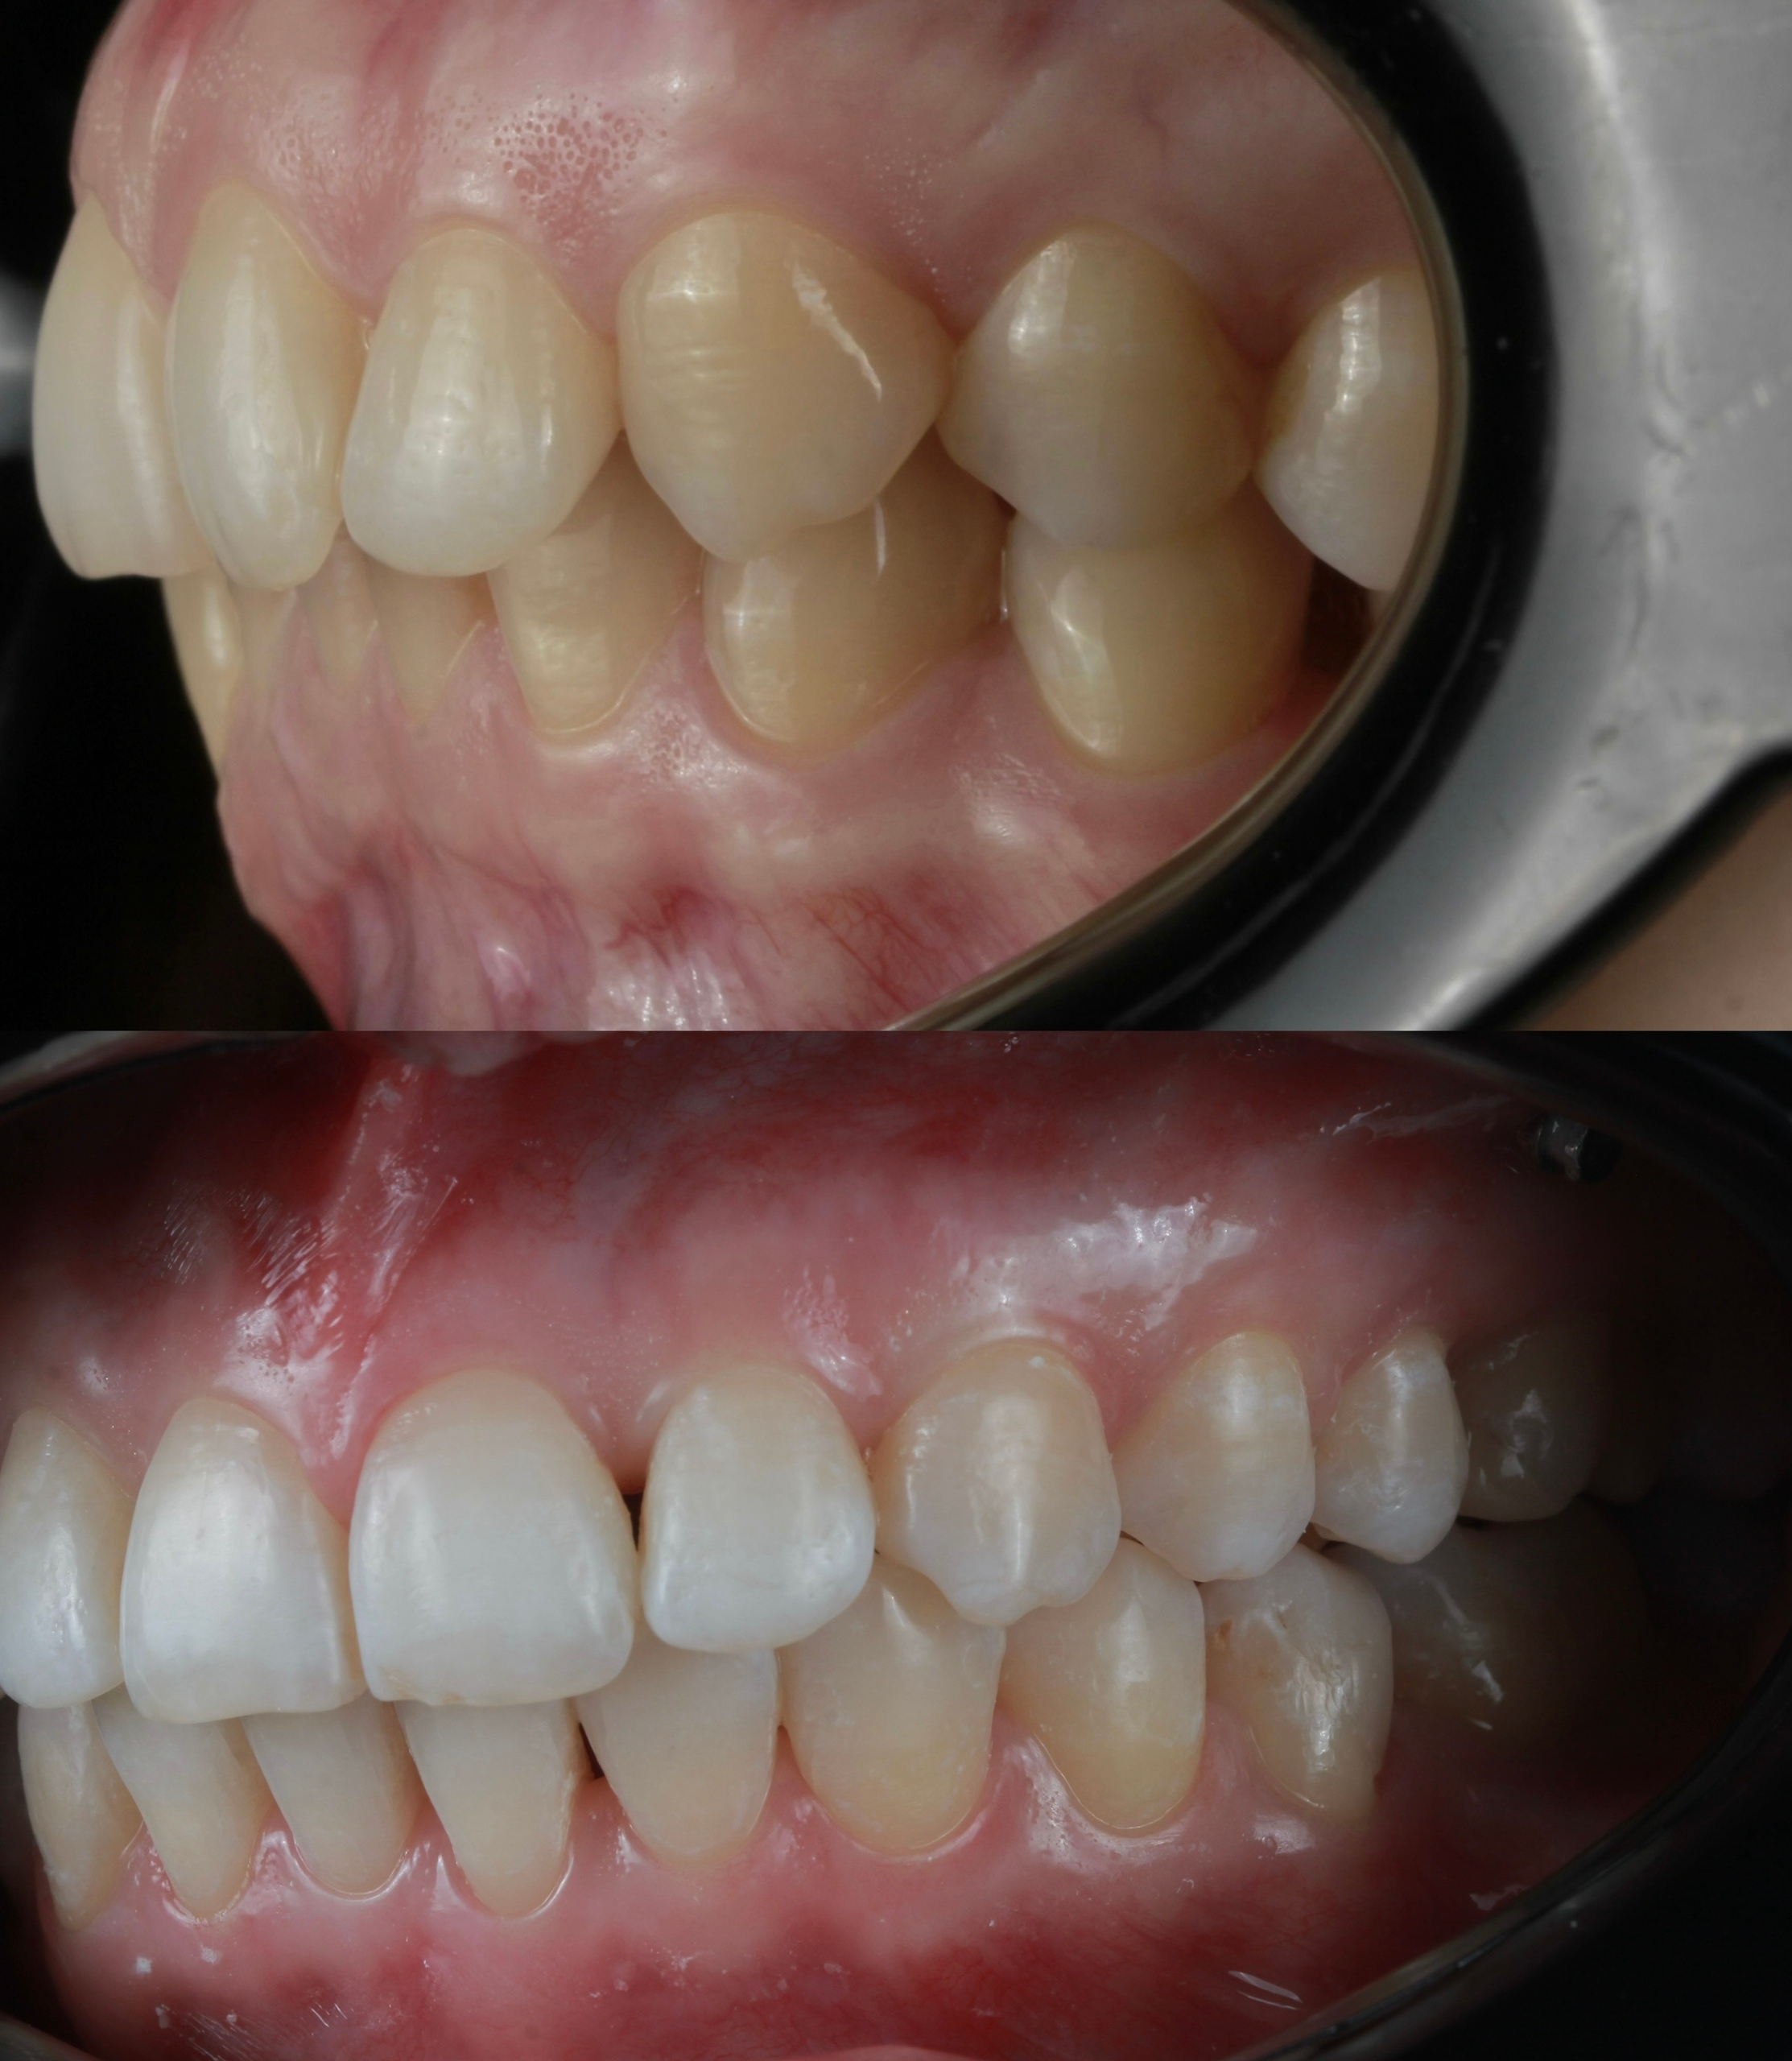

Клинический случай:

Рассмотрим пример ортодонтической коррекции на брекет-системе Damon Q. В данном случае срок лечения составил 1 год и 10 месяцев. За этот период удалось решить несколько важных задач:

• Устранение скученности зубов

• Коррекция наклона верхнего зубного ряда

• Удаление сильно разрушенного зуба на нижней челюсти и закрытие образовавшегося промежутка своими зубами

• Откорректированный прикус и центры зубных рядов

Работа была выполнена врачом-ортодонтом Глуховой Т.А., который тщательно подошел к каждому этапу лечения, чтобы достичь оптимального результата.